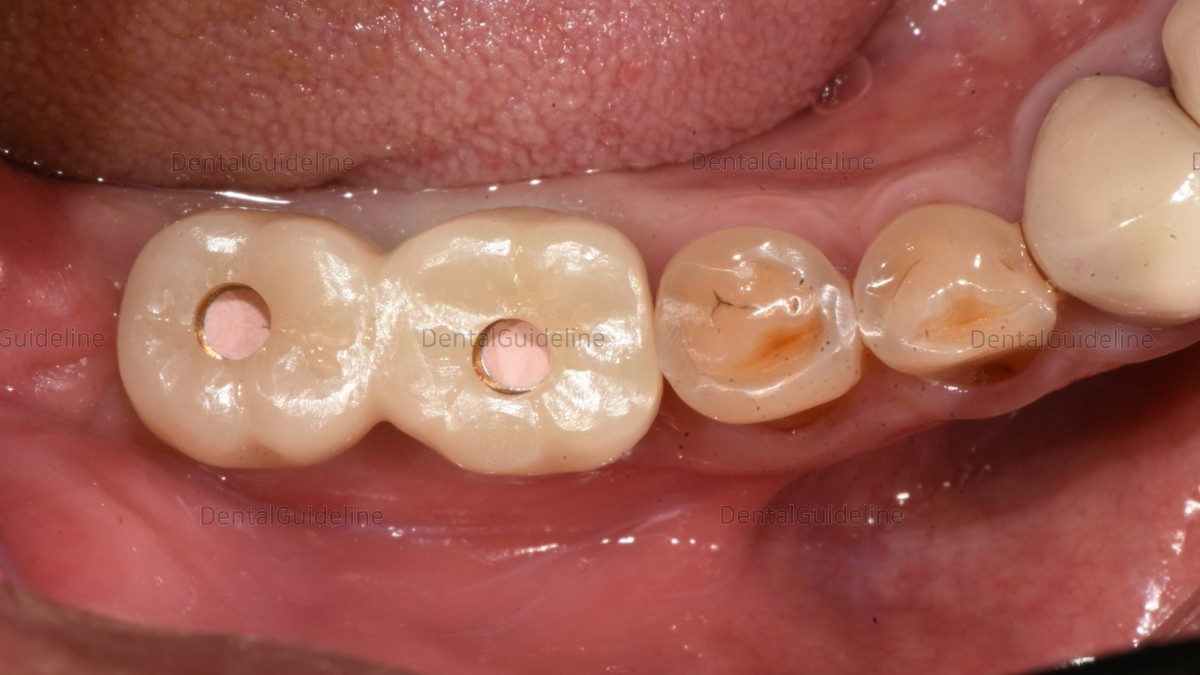

Customized abutment and crown (zirconia)

abutment connection and screw hole filling